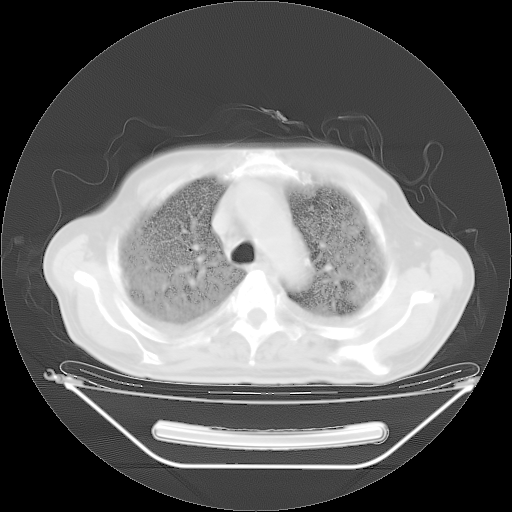

今天复查肺部CT,发现双肺广泛磨玻璃样改变。所以我把3月19日和5月9日相隔50天的肺部CT上传。请大家会诊。

2009年3月19日肺部CT片。

5月9日肺部CT(在4月27日齐鲁医院肺部CT描述部分肺组织磨玻璃样改变,12天后肺组织广泛磨玻璃样改变)